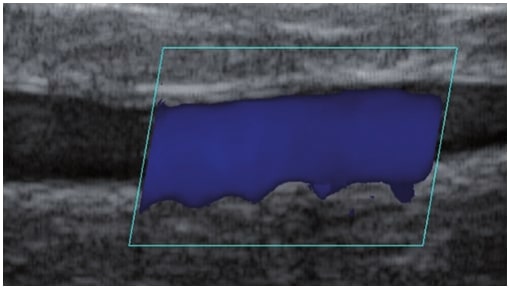

La sonographie Doppler permet l’imagerie des gros vaisseaux et des perforantes qui sont généralement situés dans les couches plus profondes du tissu sous-cutané (fig. 1). Malheureusement, la sonographie conventionnelle n’est pas capable d’imager les vaisseaux plus petits. Afin de visualiser les vaisseaux plus petits situés près de la surface de l’épiderme et dans la couche supérieure du tissu sous-cutané, l’EHF est utilisée (fig. 1). Grâce à l’utilisation de transducteurs dont les fréquences sont supérieures à 20 MHz, une image échographique à haute résolution est obtenue dans laquelle nous pouvons différencier des structures qui sont plus petites que 0,1 mm. Cependant, plus la résolution est élevée, moins la pénétration du faisceau ultrasonore dans les couches de la peau est profonde. Par conséquent, selon le transducteur et l’appareil, il est possible de pénétrer la peau jusqu’à une profondeur maximale de 20–30 mm. Une telle pénétration, associée à une haute résolution d’image, permet l’évaluation de vaisseaux sanguins même très petits (fig. 2). Pendant l’examen avec l’utilisation de transducteurs à haute fréquence, on peut évaluer avec précision le trajet et l’emplacement des petits vaisseaux dans la peau. Cela est particulièrement pertinent pour la sélection de la méthode de fermeture des vaisseaux et la planification de la procédure, car en pratique, la surface de la peau ne montre très souvent qu’un petit nombre de vaisseaux ou un léger fragment de vaisseau – ce n’est qu’après l’examen US que nous pouvons déterminer leur nombre réel et leur trajet. Pour une fermeture efficace du vaisseau, il est nécessaire de le faire sur toute sa longueur. Elle ne doit pas se limiter au fragment vu « à l’œil nu » à la surface de la peau, car la fermeture du fragment entraînera sa recanalisation rapide(7). Fréquemment, le vaisseau visible à la surface de la peau change de trajet, devient plus tortueux et se déplace vers les couches plus profondes de la peau(8). Par conséquent, le trajet de la veine et des perforantes doit être bien connu et déterminé avant la procédure. L’EHF permet également l’imagerie des perforantes entre les petits vaisseaux. De plus, outre l’évaluation du trajet et de l’anatomie, l’image échographique, grâce au logiciel d’échographie, permet également de déterminer les paramètres de base tels que le diamètre du vaisseau, l’épaisseur de sa paroi, la profondeur dans la peau ainsi que la présence ou l’absence de perfusion à l’intérieur du vaisseau(6) (fig. 3). Grâce au transducteur électronique multi-éléments d’une fréquence de 40 MHz introduit sur le marché par Ultrasonix, il est également possible de visualiser la perfusion des vaisseaux en mode Doppler couleur (fig. 4).